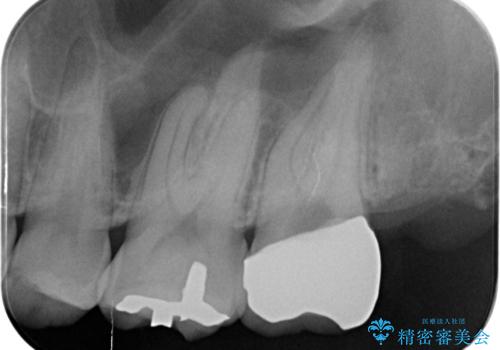

奥の虫歯 ジルコニアクラウンでの修復

- 奥歯が欠けてしみるとのことで来院された患者様です。

かなり大きな虫歯であることと、清掃不良により歯全体が脱灰していたため、クラウンでの修復処置を行います。

奥に生えている親知らずも清掃不良であったため、今回治療する歯の清掃性を高めるために抜歯を行います。

かなり大きな虫歯でしたが症状も出ず、根管治療もせずに終えることができました。